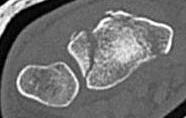

Fracture configurations

| Extra-articular fracture | Intra-articular with scaphoid and lunate fossa fragments | Volar Barton's |

![]() |